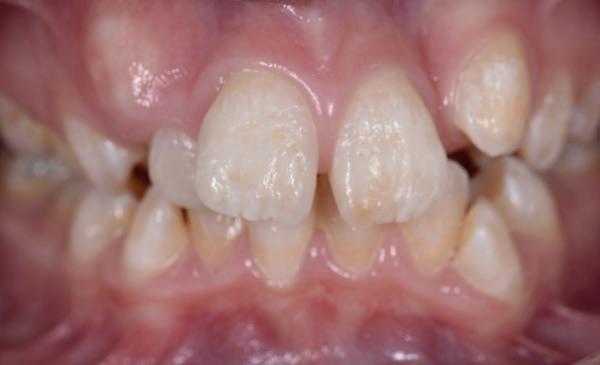

De kwetsbaarheid van het onderfront

Vooral in het mandibulaire front, waar het bot van nature dun en smal is, zijn de risico’s het grootst.

Klinische observaties en literatuur (o.a. Teughels et al., 2009; Engelking & Zachrisson) tonen aan dat zodra de wortel van een element buiten het corticale bot wordt gebracht, het lichaam deze positie niet corrigeert met spontane botgroei. In plaats daarvan treedt botresorptie op, gevolgd door mucogingivale problemen. Patiënten die jaren na een orthodontische behandeling terugkomen met gingivarecessies, mobiliteit of wortelcariës blijken vaak onbewust slachtoffer van een (soms door retentie versterkte) standswijziging die torque-gerelateerd is. Met name bij een dun gingivaal biotype is de biologische tolerantie minimaal.

1. Onderfront pre-orthodontisch: zichtbare gingivarecessie bij de 31 ten gevolge schending van de biologische envelop.

2. Occlusale opname onderfront: standswijzigingen bij de 32 en de

31 door een geactiveerde retentie draad.

3. (Lokale) orthodontie leidt tot adequate standscorrectie met afname van de gingivarecessie bij de 31

problematiek. Hoewel bedoeld om stabiliteit te waarborgen, fungeert de retentiedraad bij loslating of vervorming geregeld als actieve orthodontische krachtbron. Elastic deflection of spanningsopbouw door parafunctie kan ongecontroleerde bewegingen veroorzaken waarbij tanden letterlijk “schommelen” rond een verstoorde as. Het gevolg: wortels die buccaal of linguaal buiten de botbegrenzing worden gedrukt met parodontale schade als gevolg.